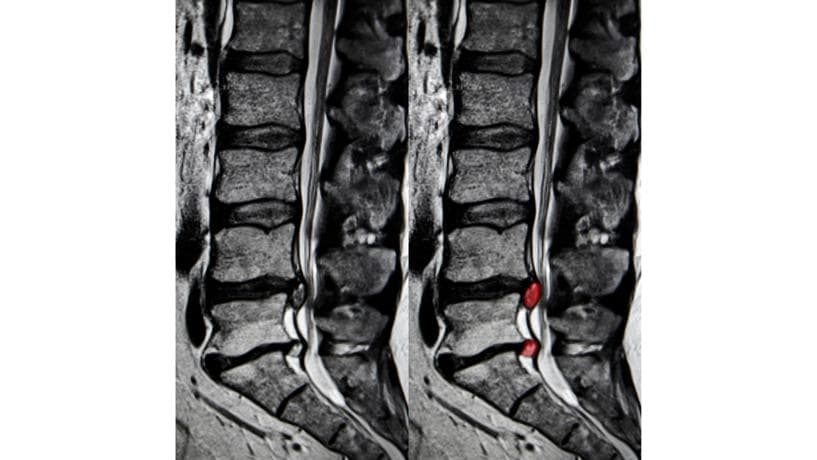

腰椎椎間板ヘルニアとは、椎骨と椎骨の間にあるクッションの役割を果たす椎間板の内部にある「髄核」というゲル状の組織が、外に飛び出して神経を圧迫する状態を指します。特に第4腰椎と第5腰椎の間、第5腰椎と仙骨の間で発症しやすく、20~30代の若い男性に多いのが特徴です。